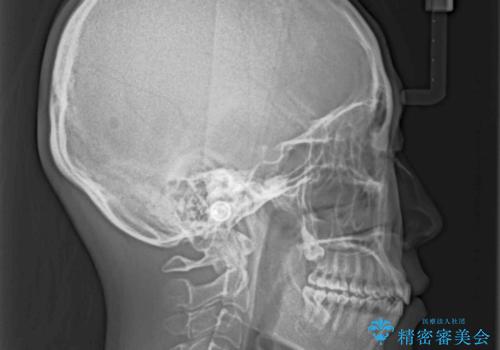

前歯の叢生とオープンバイト インビザラインでの矯正治療

- 前歯の開咬を気にして来院された患者様です。

開咬の治療は、前歯を閉じるように動かすとともに、上下臼歯を圧下(骨内にめり込ませる)させることで進めて行きます。

インビザラインは臼歯の圧下を効果的に行えるため、インビザラインを用いて矯正治療を行うこととしました。